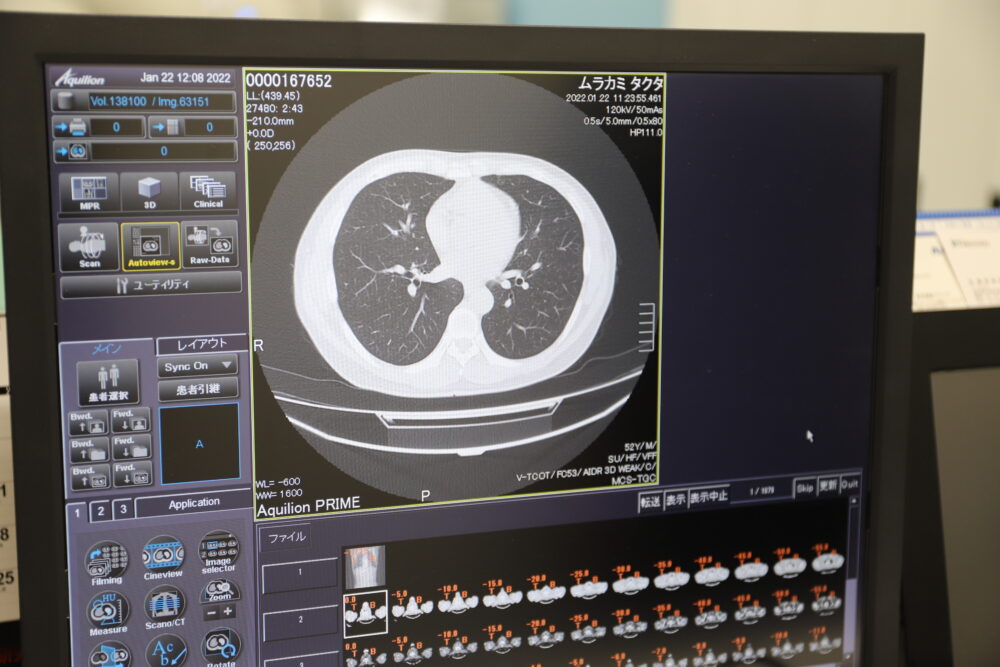

などと思ってるうちに、検査は終わる。病院のモニターには私の輪切り画像が何百枚と保存されている。この輪切り画像から、閲覧用の画像が合成されるとのこと。

肺の中身が丸見えだ。昨今のニュースで肺の炎症度合などが見られているような画像ですね。自分の身体の中がこうやって見えるって本当に不思議な感じです。